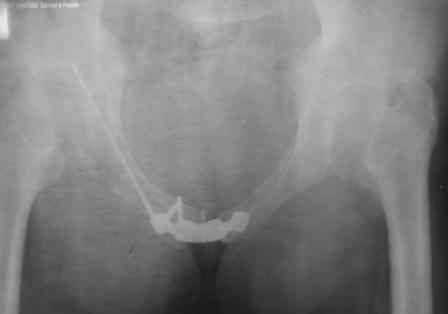

в архиве нашел подобный случай

С Уважением А.Миронов(Новокузнецк)